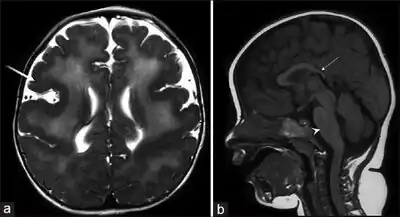

Magnetic resonance imaging of the brain shows abnormalities of the corpus callosum and cortical dysplasia, with pachygyria and polymicrogyria.